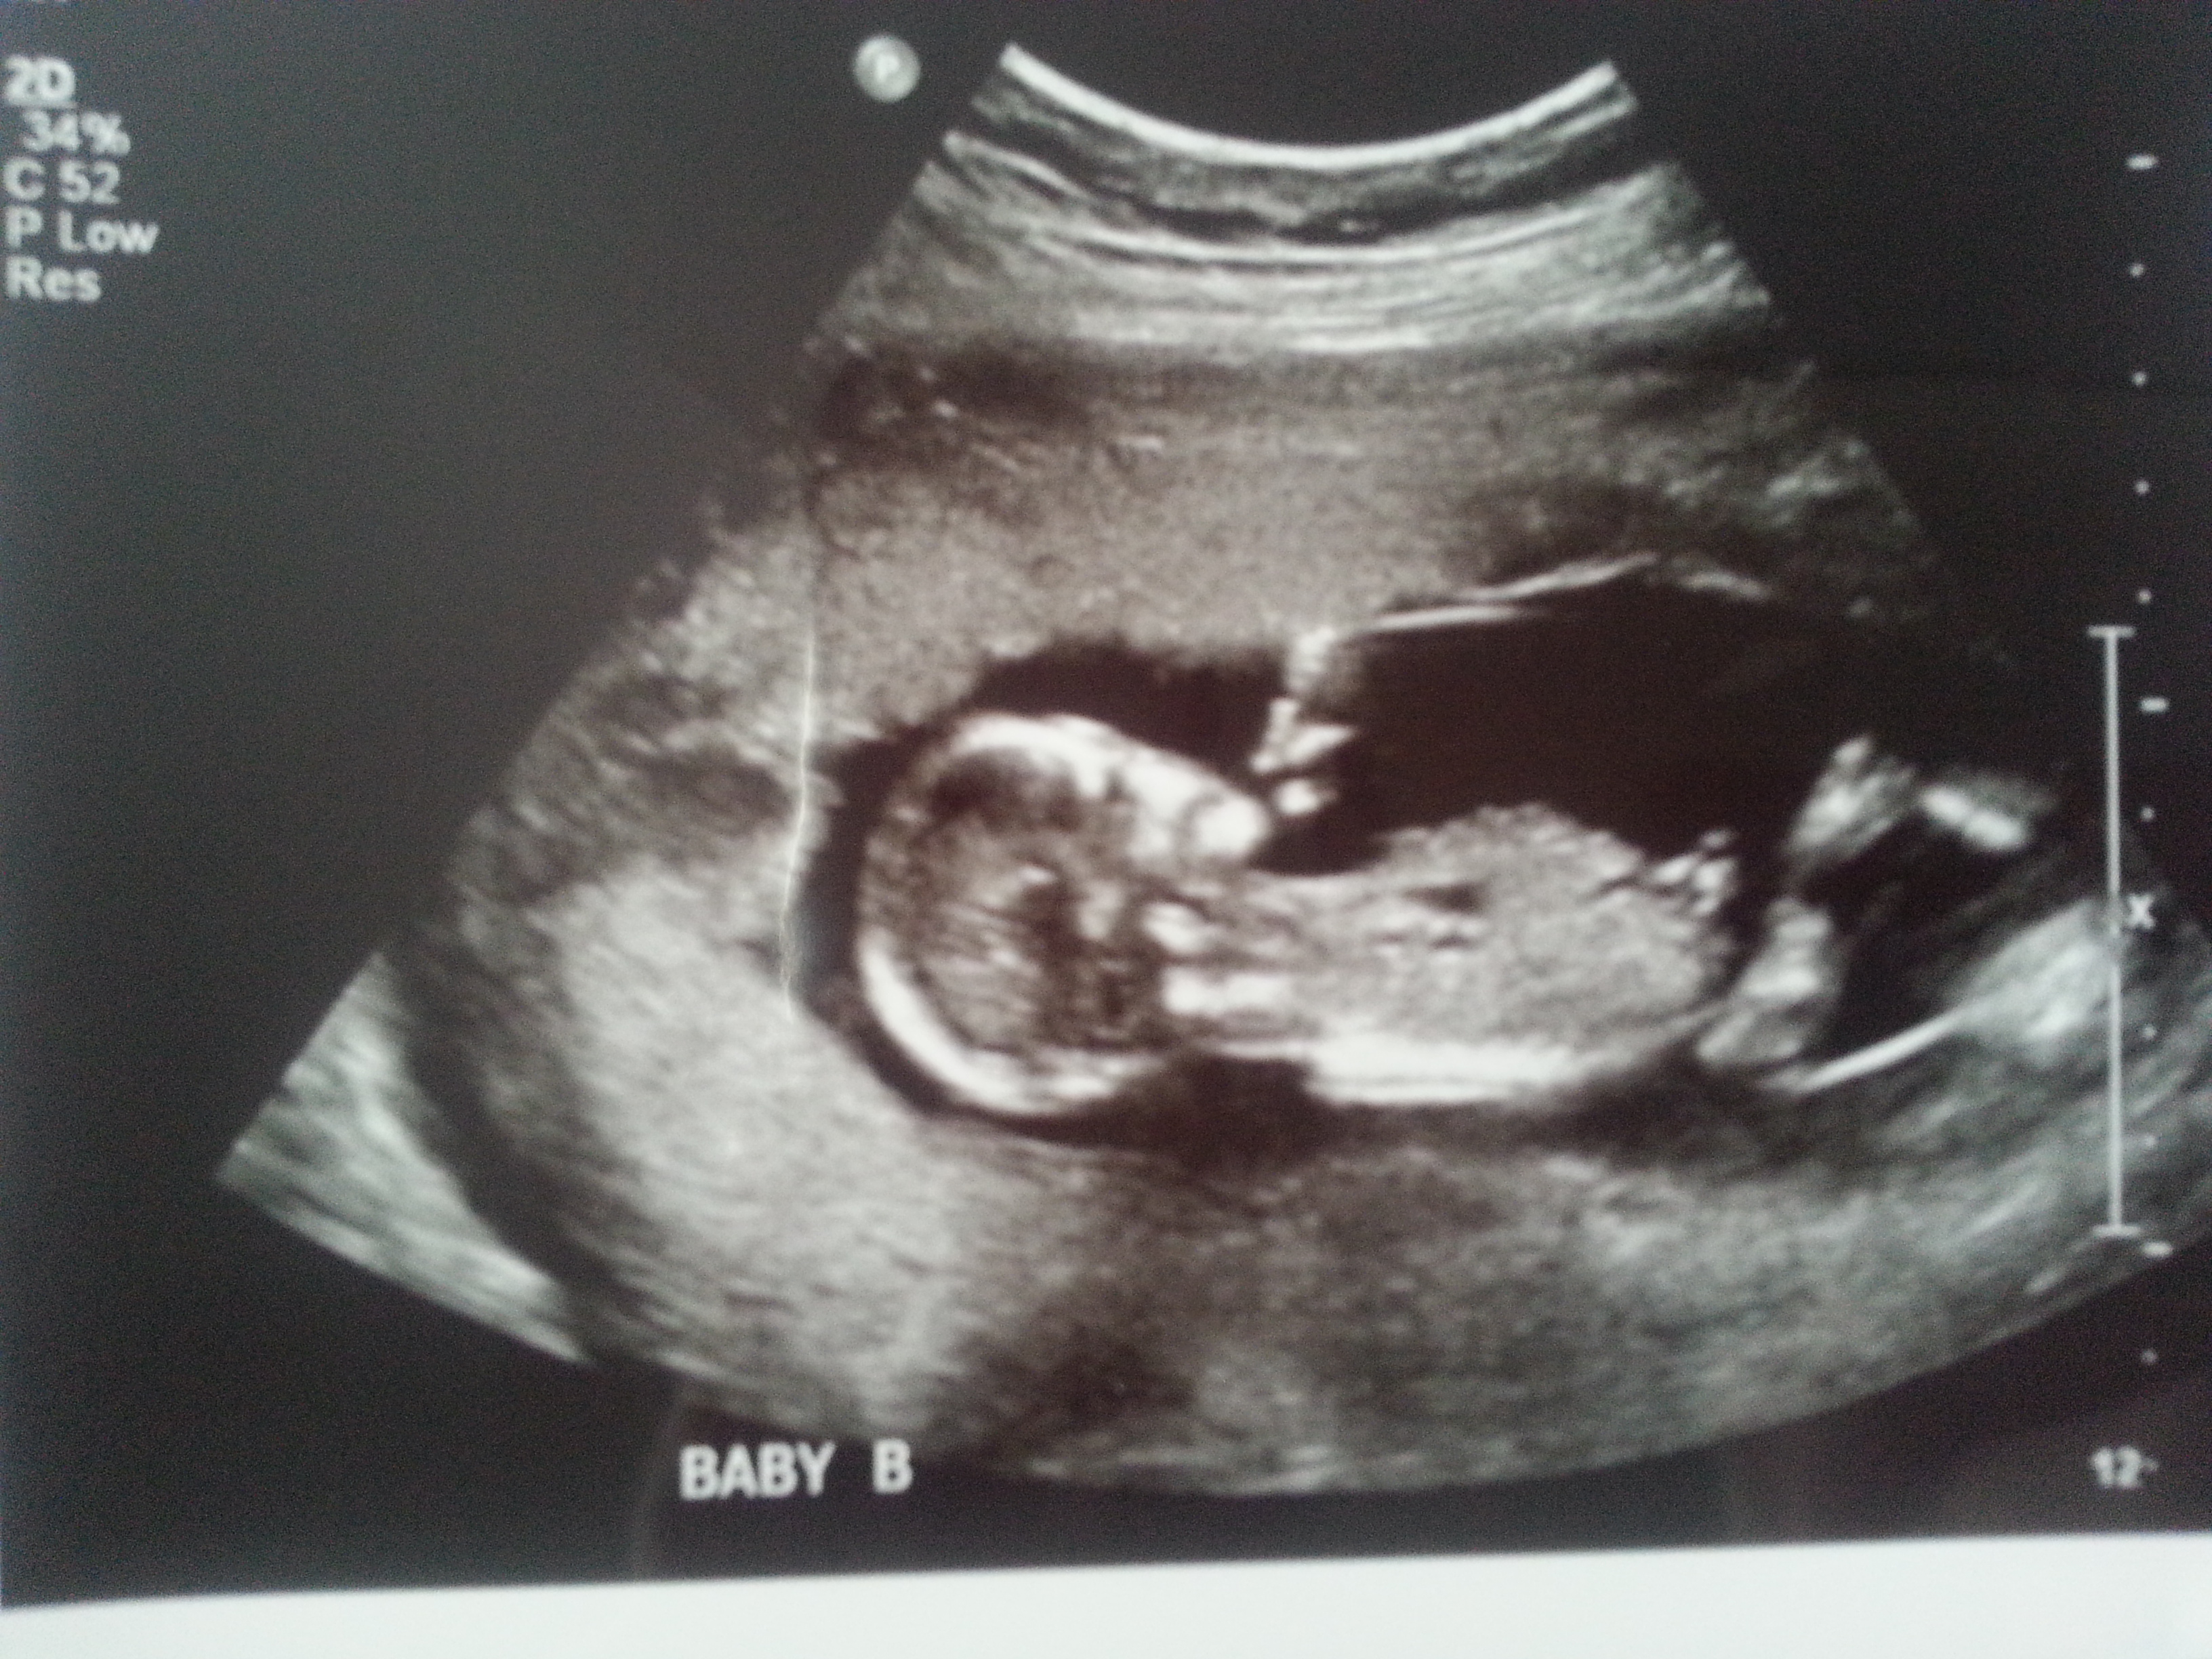

I was 12weeks 6 days and measuring 13weeks 3 days.

Attachment 23435

Maybe boy/girl. Not the best shots though!

I think I'm seeing a very boyish nub for baby B. Baby A not as sure. I hope that's your girl! Congrats and good luck!

On your second pic of baby B I'm looking at the little line between the legs that's almost sticking straight up.... very boyish "angle of the dangle".

Yip I stand by my Girl twin A and Boy lean twin B X

I'd guess boy/girl too. Baby B looks really boyish. Baby A is more questionable, but at 13 weeks, I'll lean girl.

I think B is def a boy. A has a boyish skull but girly nub. I'd go with the nub though and lean girl! Congrats on your twins!